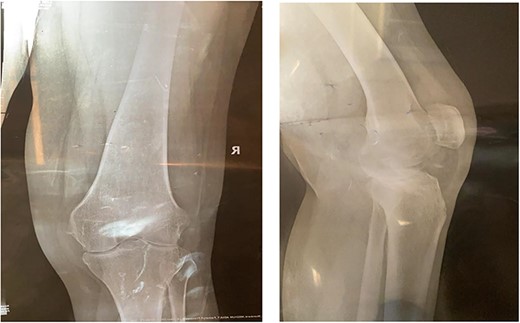

CT demonstrated extensive heterotopic ossification involving the popliteal fossa, the anterior surface of the patella and at the distal third of anterior femur extending to the level of the knee-replacement prosthesis. There was no evidence of implant looseness or alignment deformity and there was no evidence of progressive ossification.